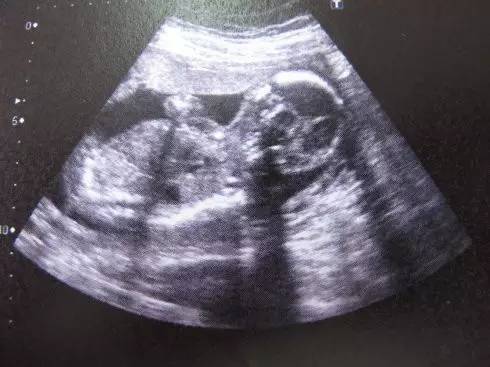

NO.1【B超】

B超就是利用超声波了解体内结构的一种观察仪器。

B超最早采用的是黑白超声诊断技术,通过发射超声波,使超声波遇到屏障产生回声,利用电脑收集这些回声,转化为相应的图像在屏幕上显示出来。通过超声探头测得的图像是黑白的,只能观测到胎儿的组织结构,测量头有多大、身有多长。